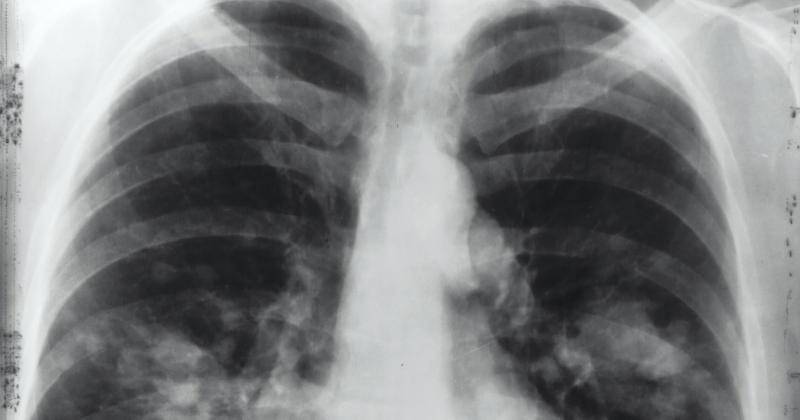

Badan Internasional untuk Penelitian Kanker WHO (IARC) merilis studi yang menyebut tren kenaikan kanker paru-paru bagi non perokok. Dalam studi itu disebut juga bahwa kanker paru-paru pada orang yang belum pernah merokok sekarang diperkirakan menjadi penyebab kematian akibat kanker tertinggi kelima di seluruh dunia.

Informasi saat ini, kanker paru-paru masih menjadi jenis kanker yang paling sering terjadi dan penyebab utama kematian akibat kanker di dunia.

Pada tahun 2022 sendiri sekitar 2,5 juta orang menerima diagnosis penyakit ini. Namun, pola kejadian berdasarkan subtipe kanker telah mengalami perubahan signifikan dalam beberapa dekade terakhir.